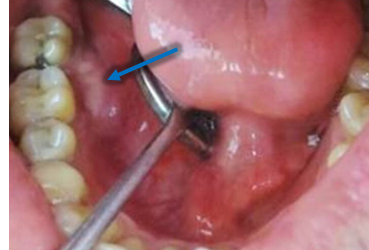

A 30-year-old male patient presented with the chief complaint of swelling in the right second molar area for past 7 months.

Benign Neoplasm